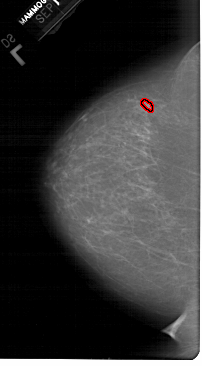

A_1549_1.LEFT_MLO

LEFT_MLO LINES 6646 PIXELS_PER_LINE 3631 BITS_PER_PIXEL 12 RESOLUTION 43.5 OVERLAY

FILE: A_1549_1.LEFT_MLO.OVERLAY

TOTAL_ABNORMALITIES 1

ABNORMALITY 1

LESION_TYPE MASS SHAPE OVAL MARGINS ILL_DEFINED

ASSESSMENT 4

SUBTLETY 2

PATHOLOGY BENIGN

TOTAL_OUTLINES 1

BOUNDARY